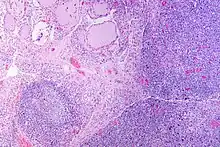

| The thyroid of someone with Hashimoto's thyroiditis as seen with a microscope at low magnification | |

Gross pathology of a thyroid with autoimmune thyroiditis may show an symmetrically enlarged thyroid.[22] It is often paler in color, in comparison to normal thyroid tissue which is reddish-brown.[22] Microscopic examination will show infiltration of lymphocytes and plasma cells. The lymphocytes are predominately T-lymphocytes with a representation of both CD4 positive and CD8 positive cells.[22] The plasma cells are polyclonal, with present germinal centers resembling the structure of a lymph node.[22] Fibrous tissue may be found throughout the affected thyroid as well.[22] Generally, pathological findings of the thyroid are related to the amount of existing thyroid function - the more infiltration and fibrosis, the less likely a patient will have normal thyroid function.[22] In late stages of the disease, the thyroid may be atrophic.[12]

Histologically, the hypersensitivity is seen as diffuse parenchymal infiltration by lymphocytes, particularly plasma B-cells, which can often be seen as secondary lymphoid follicles (germinal centers, not to be confused with the normally present colloid-filled follicles that constitute the thyroid). Atrophy of the colloid bodies is lined by Hürthle cells, cells with intensely eosinophilic, granular cytoplasm, a metaplasia from the normal cuboidal cells that constitute the lining of the thyroid follicles. Severe thyroid atrophy presents often with denser fibrotic bands of collagen that remains within the confines of the thyroid capsule.[52]

It is also characterized by invasion of the thyroid tissue by leukocytes, mainly T-lymphocytes. A rare but serious complication is thyroid lymphoma, generally the B-cell type, non-Hodgkin lymphoma.[53]